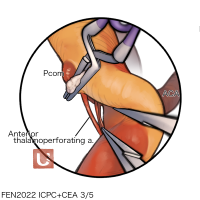

FEN2022シリーズ